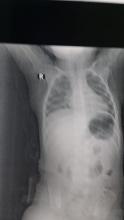

There were signs of respiratory distress (stridor). A plain chest X-ray demonstrated a radio-opaque shadow inside the trachea. A rigid bronchoscope was performed under general anesthesia, and after several attempts, a large fish bone was removed. The foreign body was found under the vocal cords, and the procedure was uneventful. The child was discharged 10 hours after bronchoscopy in a good general condition.